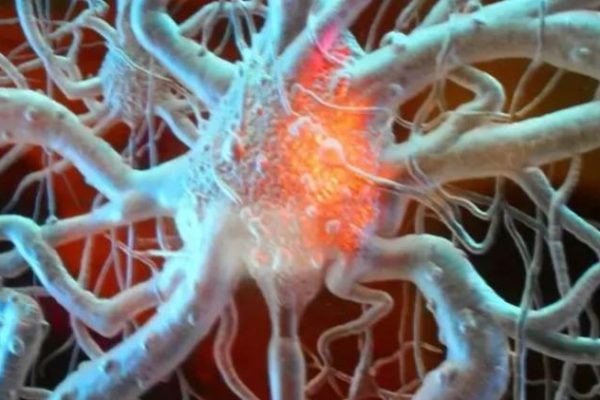

Italia, 30 ene.- Un estudio internacional identificó en células del sistema inmunitario asociadas a los tumores una potente capacidad para estimular la regeneración del tejido nervioso, lo que abre nuevas…